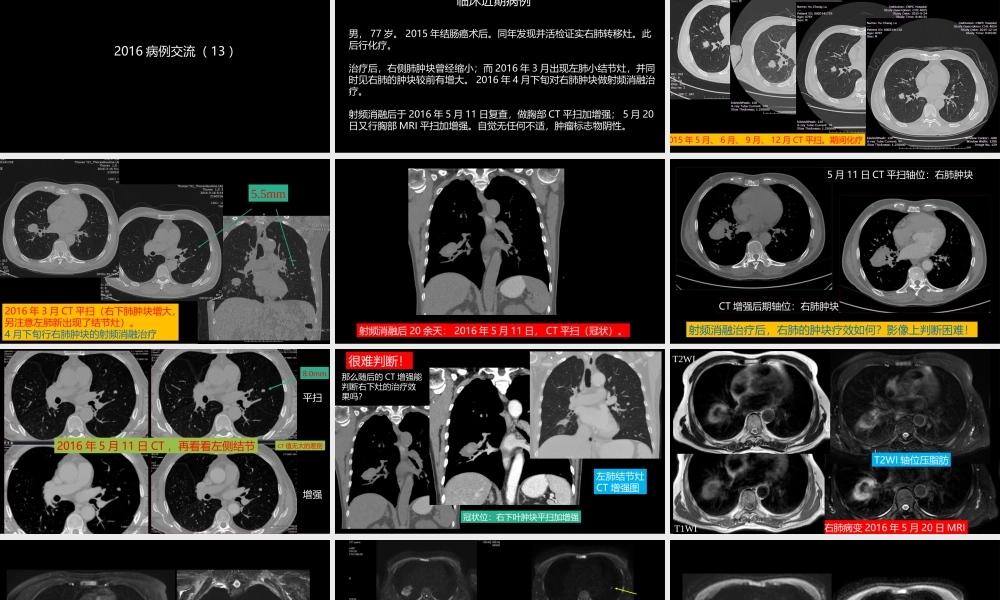

这例肺部病灶的比较影像学:价值评判中国石油中心医院影像科杨景震2016病例交流(13)临床近期病例男,77岁。2015年结肠癌术后。同年发现并活检证实右肺转移灶。此后行化疗。治疗后,右侧肺肿块曾经缩小;而2016年3月出现左肺小结节灶,并同时见右肺的肿块较前有增大。2016年4月下旬对右肺肿块做射频消融治疗。射频消融后于2016年5月11日复查,做胸部CT平扫加增强;5月20日又行胸部MRI平扫加增强。自觉无任何不适,肿瘤标志物阴性。015年5月、6月、9月、12月CT平扫。期间化疗2016年3月CT平扫(右下肺肿块增大,另注意左肺新出现了结节灶)。4月下旬行右肺肿块的射频消融治疗5.5mm射频消融后20余天:2016年5月11日,CT平扫(冠状)。5月11日CT平扫轴位:右肺肿块CT增强后期轴位:右肺肿块射频消融治疗后,右肺的肿块疗效如何?影像上判断困难!平扫增强2016年5月11日CT,再看看左侧结节CT值无大的差别8.0mm冠状位:右下叶肿块平扫加增强那么随后的CT增强能判断右下灶的治疗效果吗?很难判断!左肺结节灶CT增强图右肺病变2016年5月20日MRIT1WIT2WI轴位压脂肪T2WI左肺结节的T2WI压脂肪图:与右肺病灶的信号明显不同右侧肺肿块及左肺结节的DWI(b=800)注:ADC图中央区的低值,不要误认为扩散受限!为什么?左肺的结节扩散受限左右肺部病灶的中b值(b=150)图MRI多期增强检查:右侧肺肿物无明显强化左肺小结节MR动态增强:可见强化预扫早期中期后期MRI增强(放大图)左肺的结节灶可见强化(冠状)该病例比较其CT与MRI有以下特点本例影像学特点:1、右肺转移瘤,射频消融后CT平扫除形态学外,不能提示任何更有意义的信息,CT增强扫描可判断其呈乏血供,间接说明治疗后的变性或坏死。2、而左肺的小结节CT平扫只能比较其大小,CT增强见其强化并不明确。3、再看MRI,T2WI明确的表明右肺肿块内的结构情况:中心区出血(与CT平扫的略高密度吻合)及坏死,实际上符合肺组织这种出血性梗死的病理改变;出血周围呈富水性而无明显强化,提示治疗后的坏死或变性改变。4左肺小结节灶DWI扩散受限MR动态增强可见强化具有定性(右肺转移瘤4月下旬射频消融后;左肺结节未做治疗)END